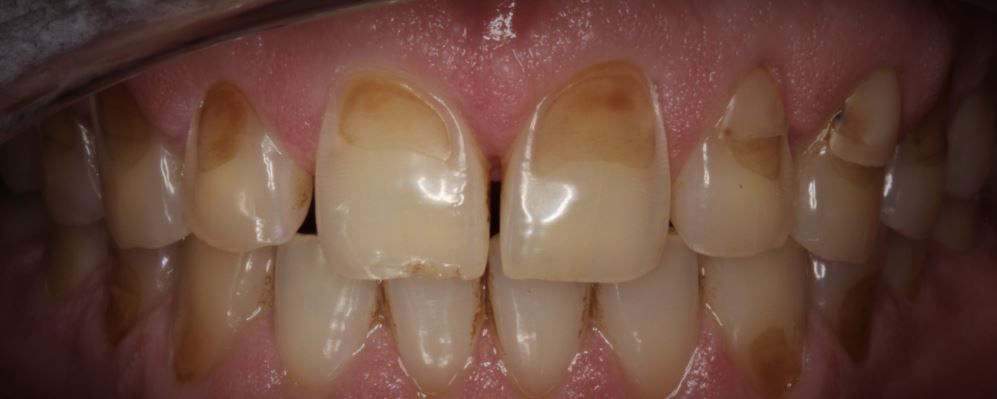

Dental erosion is the loss of tooth enamel usually caused by acidic foods and drinks attacking our teeth however there are also medical conditions such as acid reflux/indigestion and bulimia that can cause dental erosion. When enamel is worn away, the darker dentine underneath is exposed, which can lead to sensitivity and pain which can be unpleasant.

- Discoloration

- Transparent or sandblasted appearance.